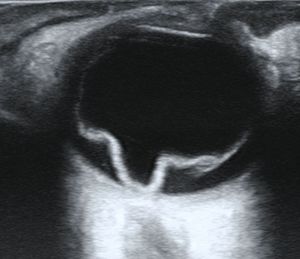

망막의 시야가 불분명한 경우, 극광각 안저 사진 촬영, B-스캔 초음파 검사, 광학 단층 촬영법 (OCT)과 같은 영상 기술이 박리를 식별하는 데 도움이 될 수 있다.[4][13][14] 안저 사진 촬영은 눈 뒤쪽을 자세히 보여주며, 망막 열공 또는 파열을 나타낼 수 있다.[4][16] B-스캔 초음파 검사에서 박리된 망막은 일반적으로 유리체강에서 떠다니는 막으로 나타나며, 파동과 같은 움직임을 보인다.[19] OCT는 망막 뒤의 체액, 황반(망막의 중심 부분)의 침범, 망막층 내의 기타 이상을 감지할 수 있다.[4][20]

망막 박리를 진단하는 표준 검사는 간접 검안경검사를 사용하여 눈 뒤쪽을 확인하는 산동 안저 검사이다.[4][10][13] 이는 종종 공막 압박이라고 하는 기술을 포함하며, 이는 전체 망막을 명확하게 볼 수 있도록 돕는다.[4][10][14] 눈 앞부분에 대한 세극등 현미경 검사에서도 망막 열공을 나타낼 수 있는 셰퍼 징후라고 하는 작은 색소 입자가 나타날 수 있다.[4][9][10]망막의 시야가 불분명한 경우, 극광각 안저 사진 촬영, B-스캔 초음파 검사, 광학 단층 촬영법 (OCT)과 같은 영상 기술이 박리를 식별하는 데 도움이 될 수 있다.[4][13][14] 안저 사진 촬영은 눈 뒤쪽을 자세히 보여주며, 망막 열공 또는 파열을 나타낼 수 있다.[4][16] B-스캔 초음파 검사에서 박리된 망막은 일반적으로 유리체강에서 떠다니는 막으로 나타나며, 파동과 같은 움직임을 보인다.[19] OCT는 망막 뒤의 체액, 황반(망막의 중심 부분)의 침범, 망막층 내의 기타 이상을 감지할 수 있다.[4][20]